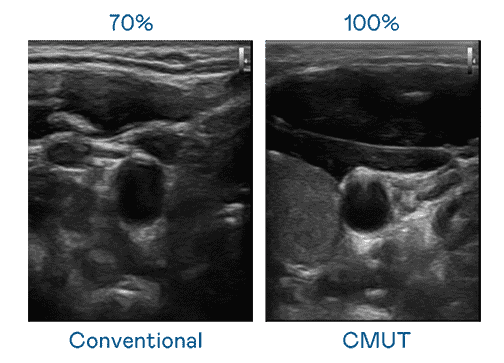

CMUT 技术是一种用电容式微机电元件来产生超音波讯号的技术。。。与传统 PZT 压电式技术相比,,,CMUT 频宽增加 30%,,更宽频的超音波讯号让影像解析度大幅提升,,,,是实现高影像品质医疗超音波扫描、、、促进精准医疗发展的关键技术。。

超音波影像的解析度高低,,,,首先取决于探头能发出的讯号频宽。。。尊时凯龙 CMUT 可提供高清晰的超音波讯号,,,,提供高频宽、、、、高灵敏度、、、、影像纹理细节更高的超音波影像,,,协助医护人员缩短影像判读时间及利用精准的医疗影像进行诊断。。